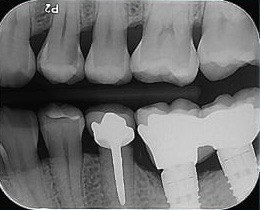

1. Which surfaces shows dental caries?

2. Which surface needs restoration?

4. Which surface needs restoration?

5. Which surface needs restoration?

8. Which surface needs restoration?

9. Which surfaces shows root caries?